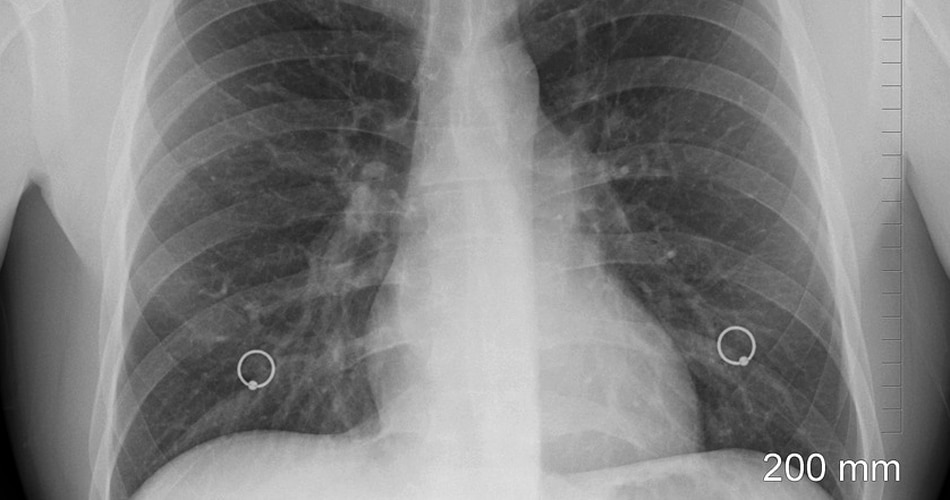

12 नवंबर को पूरी दुनिया में वर्ल्ड निमोनिया डे ( World Pneumonia Day) मनाया जाता है. इस दिन को मनाने का मकसद लोगों को निमोनिया के बीमारी के प्रति जागरूक करना है. निमोनिया में  फेफड़े संक्रमित हो जाते हैं. निमोनिया होने पर वायुकोष में तरल पदार्थ या मवाद भर जाता है जिसकी वजह से कफ, बुखार, ठंड लगना और सांस लेने में तकलीफ के साथ खांसी हो सकती है.  बैक्टीरिया, वायरस और कई तरह के सूक्ष्मजीव निमोनिया का कारण बन सकते हैं.

निमोनिया के कारण- कई रोगाणु निमोनिया का कारण बन सकते हैं. इसमें सबसे आम वो बैक्टीरिया और वायरस हैं जिन्हें हम सांस के जरिए लेते हैं. हमारा शरीर आमतौर पर इन रोगाणुओं को फेफड़ों को संक्रमित करने से रोकता है लेकिन कभी-कभी ये रोगाणु इतने मजबूत हो जाते हैं कि हमारे इम्यून सिस्टम पर हावी हो जाते हैं और शरीर को संक्रमित कर देते हैं.

निमोनिया का बैक्टीरिया जब खून के जरिए फेफड़ों में पहुंच जाता है तो ये शरीर के दूसरे अंगो को भी संक्रमित कर देता है. इसकी वजह से आर्गन फेल भी हो सकता है. गंभीर होने पर आपको सांस लेने में भी दिक्कत हो सकती है और आपको अस्पताल में भर्ती कराने की स्थिति आ सकती है.